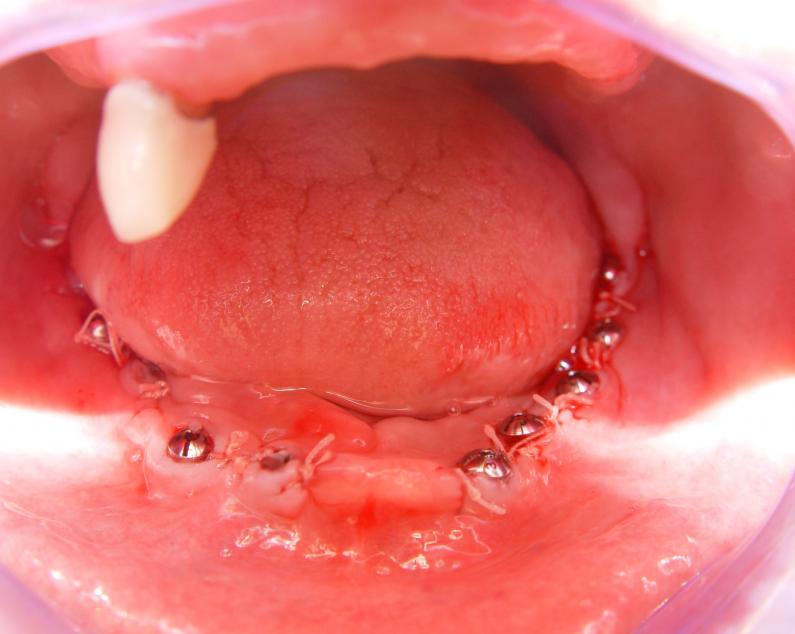

Установка 10 имплантантов на беззубую челюсть с помощью компьютерной программы: Имплантанты установлены

Имплантанты установлены

Импланта..